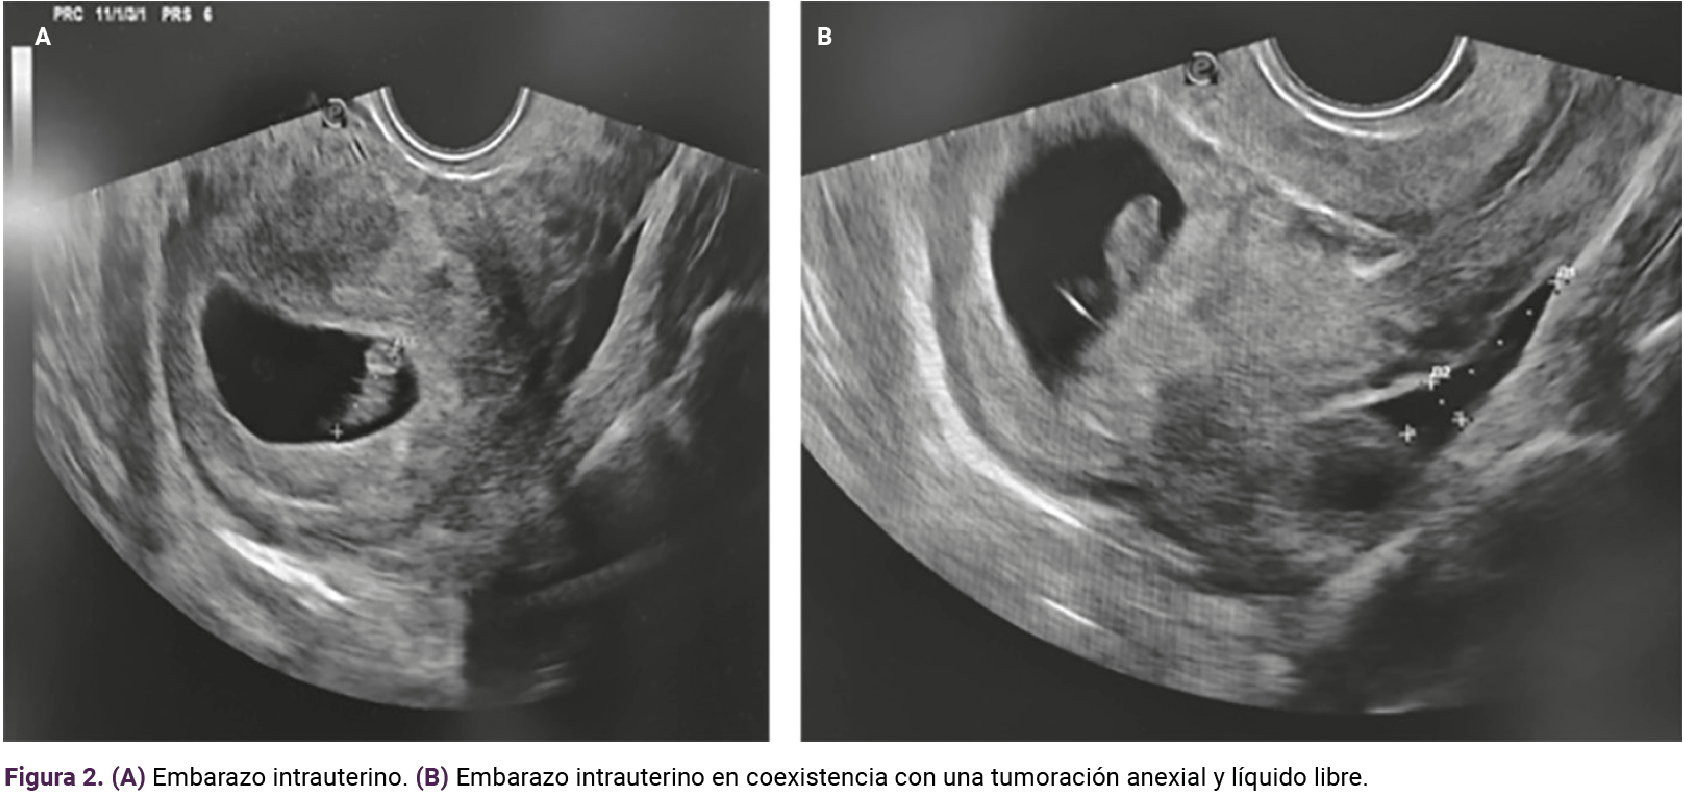

Debido a los hallazgos en la exploración física se decidió la práctica de un ultrasonido transvaginal que puso de manifiesto la existencia de una masa anexial derecha de 3 x 2 cm, con un saco con un embrión con latido cardiaco y longitud cráneo-caudal de 13.3 mm, correspondiente a siete semanas y cuatro días (Figura 1), en simultaneidad con el embarazo intrauterino. Figura 2. A y B

<strong>Figura 2</strong>.

Figura 2 A. - Figura B.